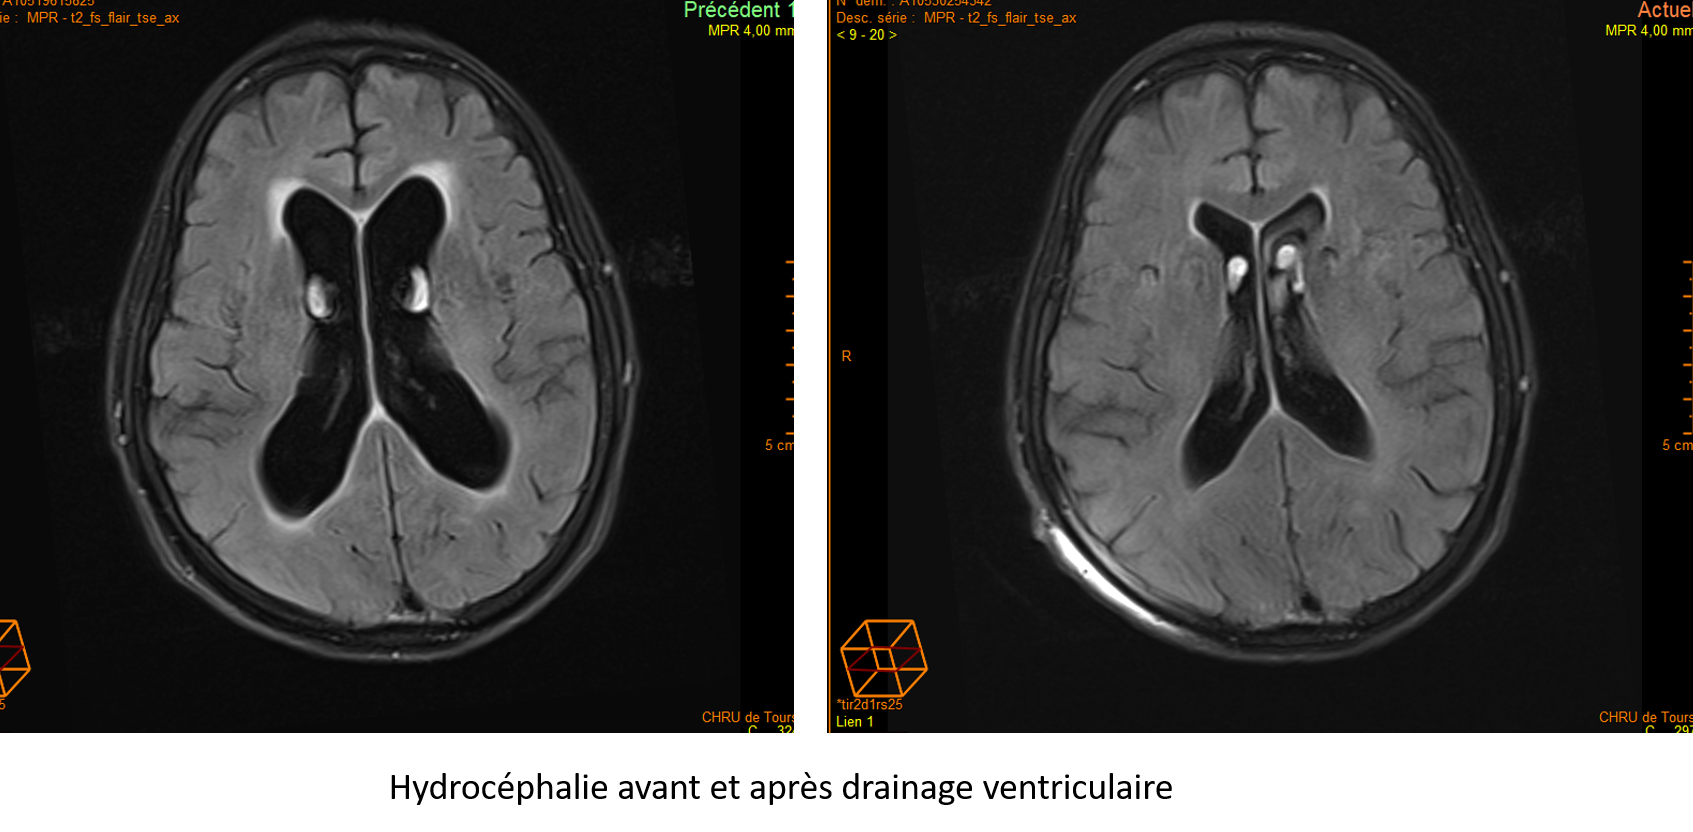

Hydrocéphalie avant et après drainage ventriculaire